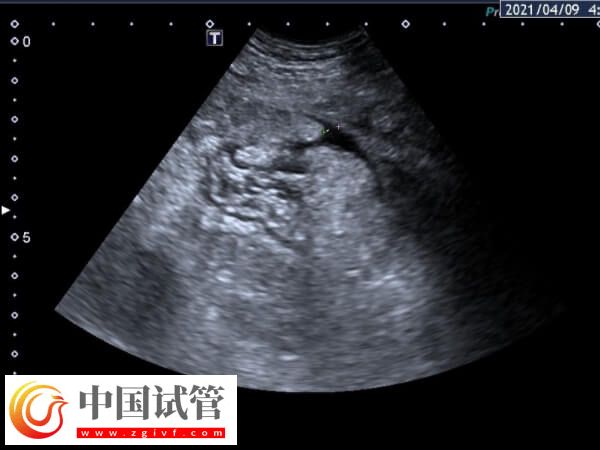

隨著不孕不育治療技術(shù)的不斷進(jìn)步,輔助生育技術(shù)逐漸成為解決不孕不育問(wèn)題的有效手段。其中,試管嬰兒治療是目前最為常見(jiàn)的輔助生育技術(shù)之一。然而,試管嬰兒治療過(guò)程中,可能會(huì)出現(xiàn)一些并發(fā)癥,其中腹水(指在腹腔內(nèi)積聚大量液體,)是較為常見(jiàn)的一種。至于腹水在取卵后多久出現(xiàn),如下所示:

取卵后腹水的高峰期通常發(fā)生在取卵后的3至10天內(nèi)。這種情況主要由卵巢過(guò)度刺激綜合征引起,此時(shí)出現(xiàn)腹水為早發(fā)型腹水,而這時(shí)出現(xiàn)的腹水,主要是由于外源性注射HCG引起,與卵巢對(duì)促性腺激素的反應(yīng)過(guò)度有關(guān)。

取卵后腹水的出現(xiàn)時(shí)間可能會(huì)根據(jù)個(gè)人體質(zhì)和治療方案的不同而有所差異。一般情況下,有的患者在取卵后12到17天內(nèi),也可能會(huì)出現(xiàn)遲發(fā)型腹水。這種腹水主要是因卵巢過(guò)度刺激綜合征引起,與促排卵藥物的使用和體內(nèi)產(chǎn)生的激素水平有關(guān)。

據(jù)研究發(fā)現(xiàn),取卵后37天是腹水高峰期。此時(shí),腹水的發(fā)生率最高,約為5%至10%。但是腹水的發(fā)生時(shí)間可能會(huì)因個(gè)體差異、手術(shù)操作技巧等因素而有所不同。有些患者可能在取卵后幾天內(nèi)就出現(xiàn)了腹水,而有些患者可能需要幾個(gè)月的時(shí)間才會(huì)出現(xiàn)腹水。